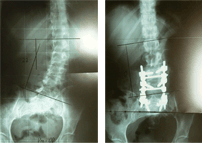

선천성 척추 기형

선천성 척추 기형 수술 전/후 X-ray

수술 전

수술 후